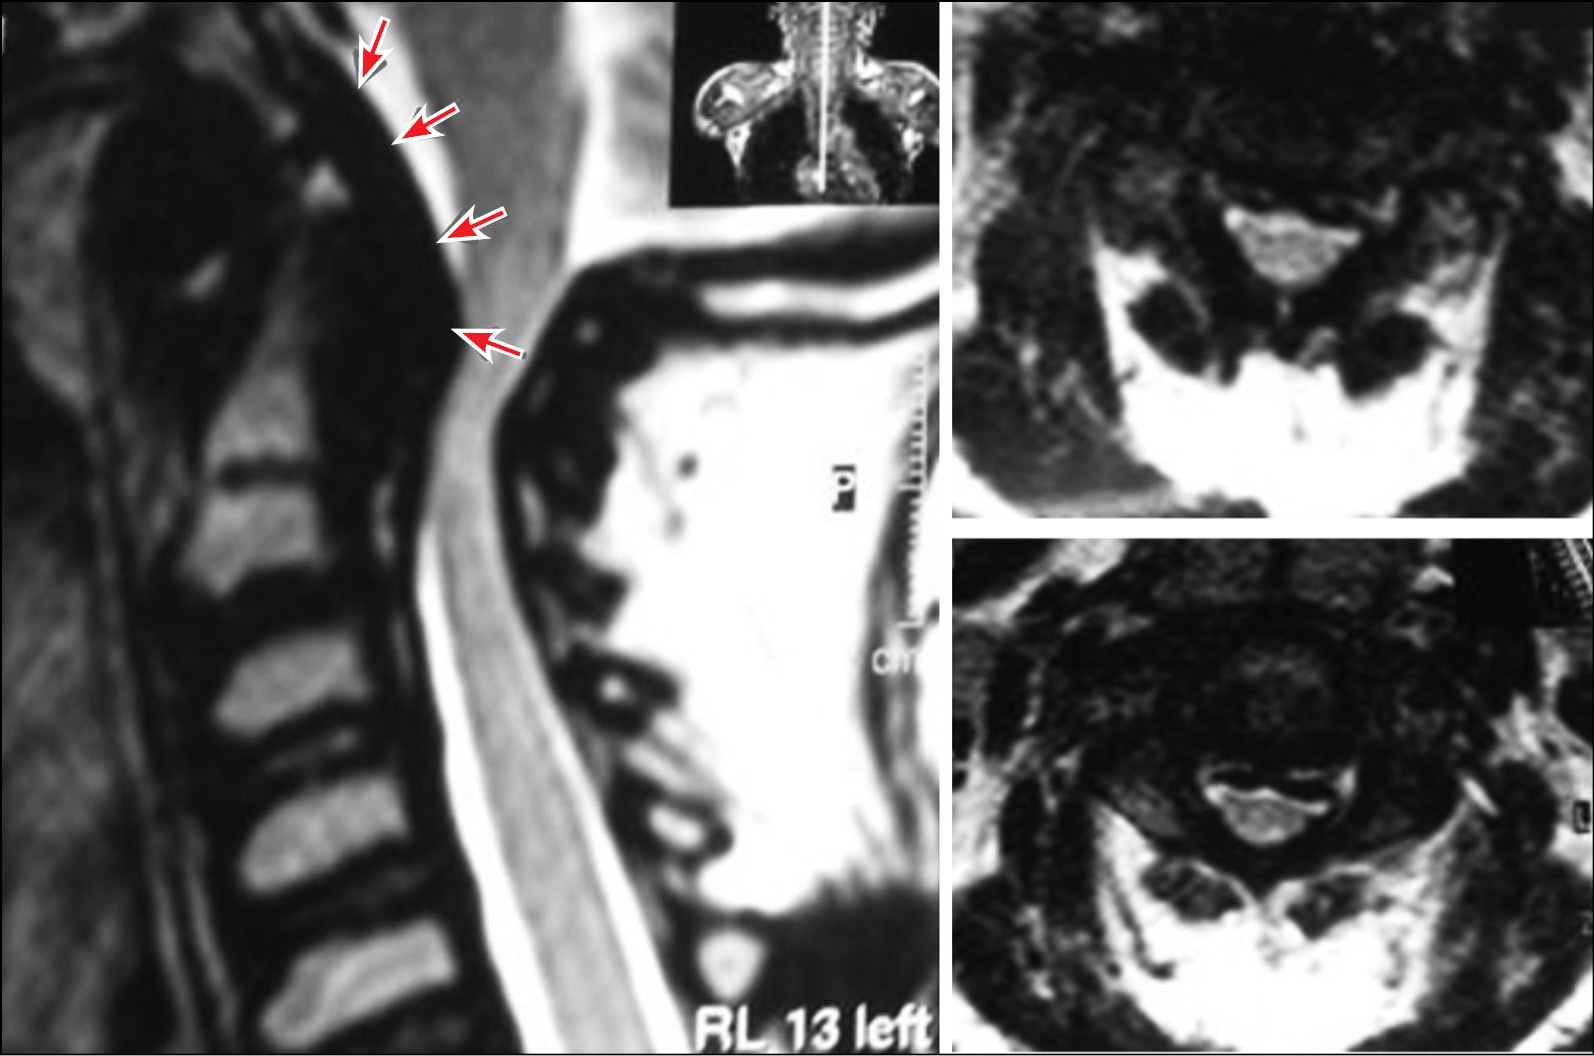

Патология диагностирована в возрасте 7 лет, когда отмечена задержка роста и появление контрактур в крупных суставах конечностей. Находилась под патронажем генетика по месту жительства. Обучалась в специализированной школе-интернате. В 10 лет в результате падения во время игры с мячом стала отмечать незначительную слабость в левой верхней и нижней конечностях. Через 6 мес. появилось снижение мышечной силы и чувствительности в верхних и нижних конечностях. Консультирована неврологом, проведено магнитно-резонансное томографическое (МРТ) исследование головного мозга — патологии не выявлено. Начата фермент-заместительная терапия (галсульфазой). С течением времени отмечалось усугубление неврологических симптомов. Выполнено МРТ шейного отдела позвоночника, на котором выявлен стеноз на уровне краниовертебрального перехода (рис. 2).

Рис. 2. Магнтино-резонансная томограмма шейного отдела позвоночника, отмечается выраженный стеноз позвоночного канала на уровне краниовертебрального перехода (стрелки)